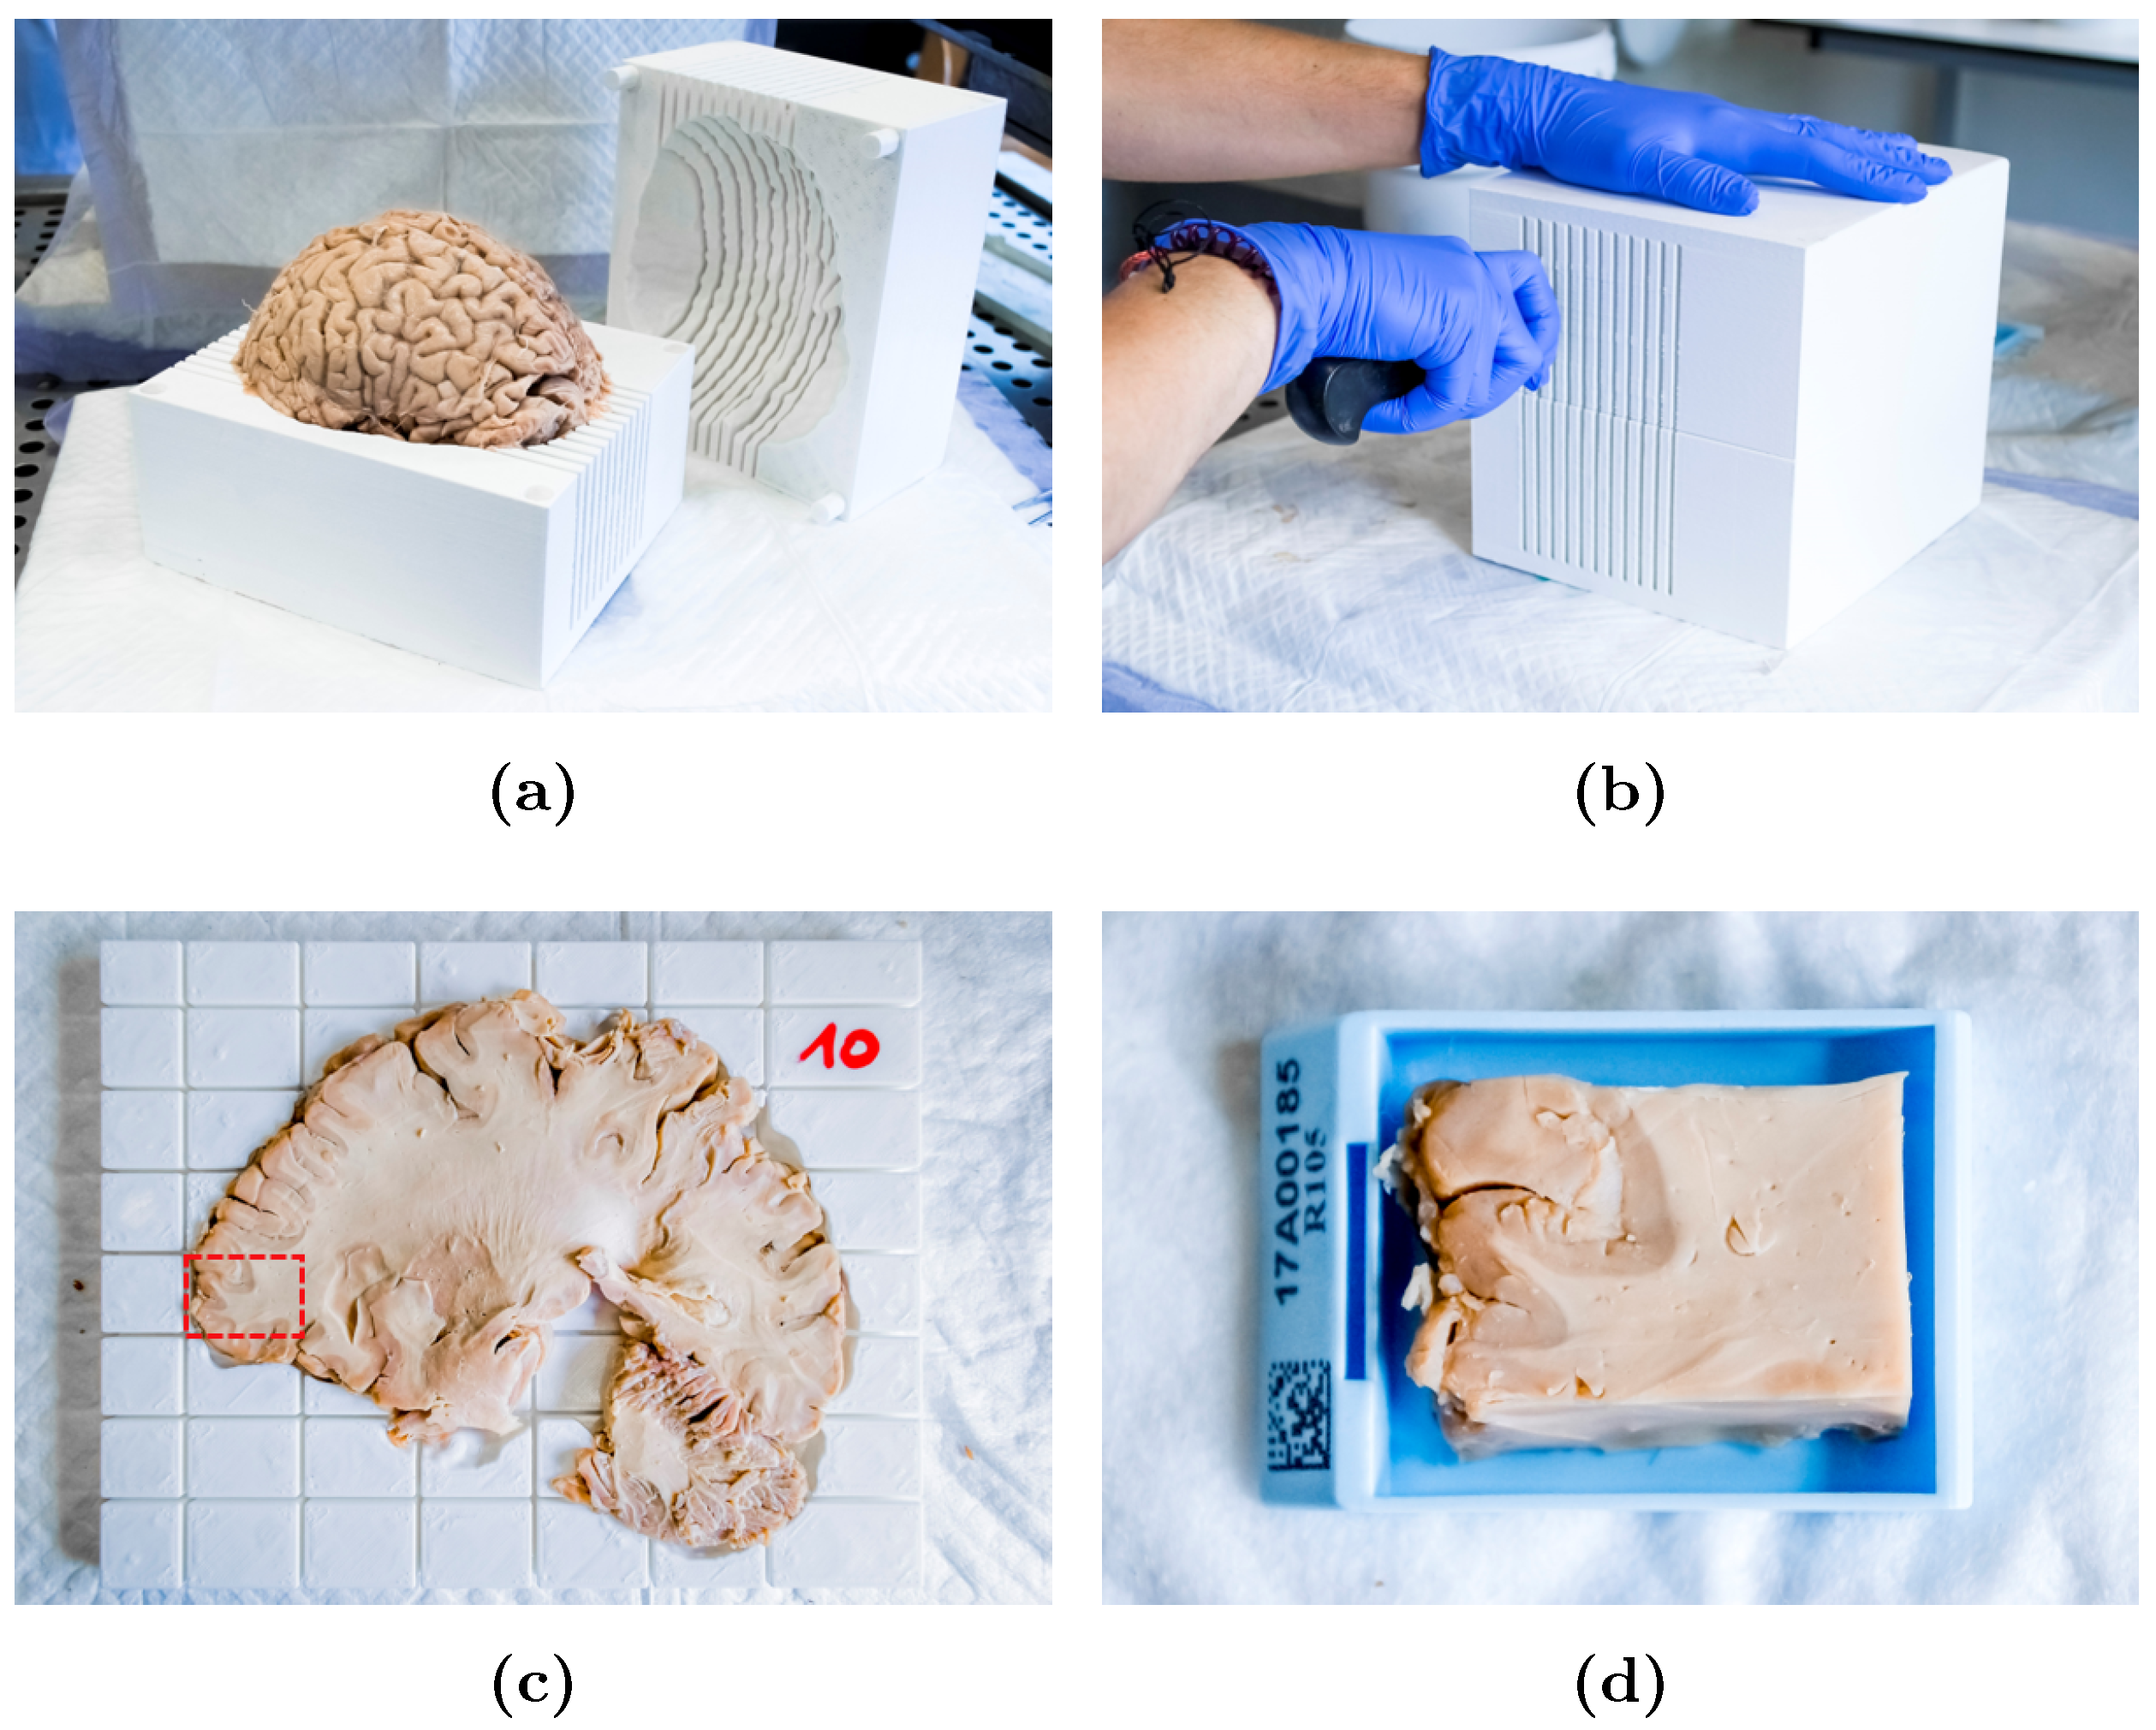

2.3. Slicer Design and Tissue Sampling

Appendix A. Slicer Design